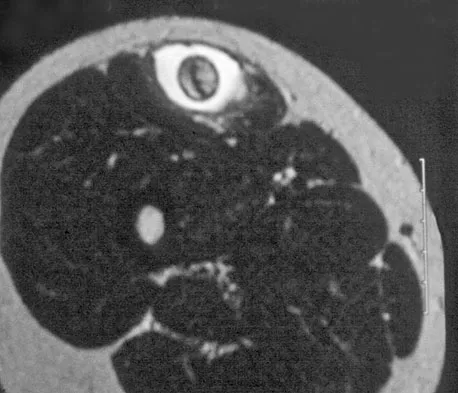

A 38-year-old man who is an avid runner reports a several month history of right hip pain. Based on the radiograph and cross-sectional CT scan shown in Figures 33a and 33b, what is the most likely diagnosis for the lesions seen on the femoral neck?

Explanation